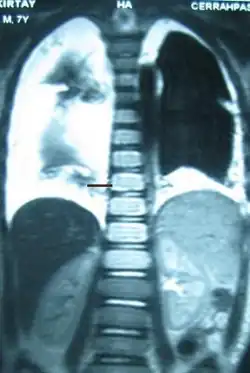

| Diagnostic method | X-ray, CT scan, thoracic MRI, fluid sampling |

The cisterna chyli can be found in a thoracic MRI, making it possible to confirm chylothorax. However, MRI is not the ideal method to scan the thorax, and so it is rarely used. Another diagnostic technique is conventional lymphangiography. It is rarely used since there are equally sensitive yet less invasive techniques available to identify a chylothorax. Lymphangiography procedures use the contrast dye agent lipiodol, which is injected into the lymphatic vessels. The chylothorax shows up on the images and identifies the source any leak in the thoracic duct.[1]